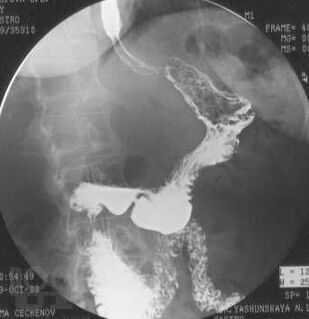

Диагностика и хирургическое лечение рака желудка

В учебном пособии приведены основные сведения об эпидемиологии, этиопатогенезе, клинике и диагностике рака желудка. Изложены морфологическая и TNM-классификации, освещены особенности метастазирования, клинического течения основных морфологических типов рака желудка. Рассмотрены тактика лечения, выбор объема операции. Изложен современный алгоритм хирургического лечения в соответствии с рекомендациями Японской ассоциации рака желудка.